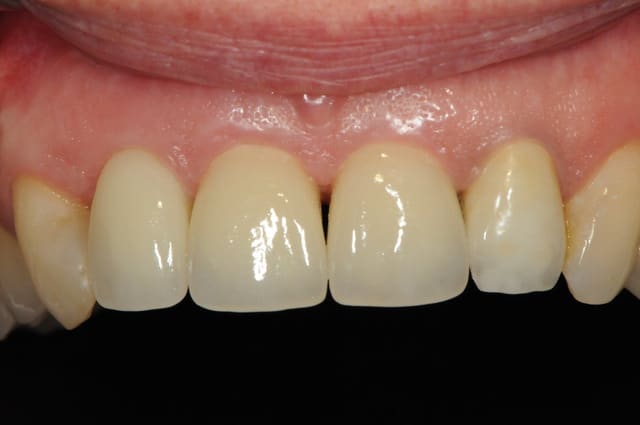

voici - voilà:

photo

1: j+ 2 ou 3 jours

2: j+8 mois

3-4-5: j+ 2 ans

sur la photo 3 on voit à la gencive que l'aspect est moins granité au niveau du col.

c'était ça l'indice pour trouver Charlie.